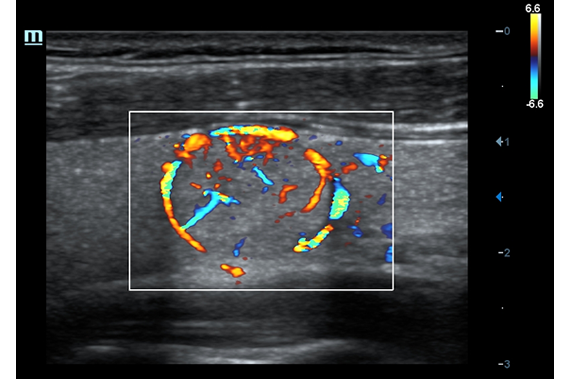

• Поддержка режимов сканирования B/M/Цветовой доплер CDI/Цветной M/Энергетический доплер PD/Направленный энергетический доплер Dir.PD.

• HR Flow - режим отображения кровотока с высоким временным и пространственным разрешением для точной и однородной визуализации сосудов, в том числе самых мелких.

Цветовой допплер:

Да